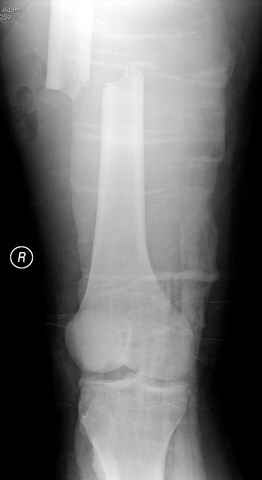

По поводу открытого перелома больной ургентно взят на ретроградное интрамедулярное штифтование, после рутинного дебрайдмента и фасциотомии на бедре и на голени.

постоперационные